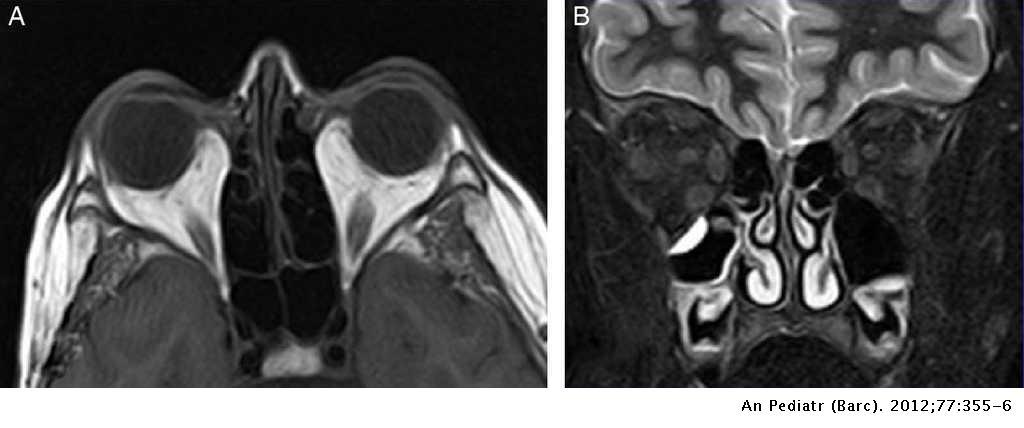

¿Cuáles son los hallazgos radiológicos en la RM de la obitopatía tiroidea?

¿Qué hallazgos radiológicos podemos encontrar en la TC del retinoblastoma?